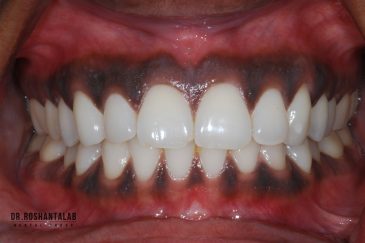

دندانپزشکی زیبایی

طراحی لبخند هالیوودی با متدهای لمینت سرامیکی دندان و کامپوزیت ونیر در کنار اصلاح فرم، خدمات بلیچینگ و روکش دندان، زیبایی چهره شما را تکمیل میکند.ترمیم دندان

برای اصلاح طرح لبخند بدون جلب توجه، از جدیدترین تکنولوژی الاینر و ارتودنسی شفاف استفاده کنید. ما تخصصیترین خدمات ارتودنسی دندان را با قیمت مناسب و شرایط اقساط ویژه ارائه میدهیم.کاشت دندان توسط بهترین متخصص ایمپلنت

انتخاب بهترین متخصص ایمپلنت که به تکنیکهای روز دنیا مسلط باشد، تضمینکننده سلامت فک و زیبایی لبخند شماست. در کلینیک دندانپزشکی دکتر روشنطلب، ما با بهرهگیری از تجهیزات دیجیتال در ۵ شعبه فعال (تهران، اصفهان، رشت و استانبول ترکیه)، خدمات تخصصی کاشت ایمپلنت دندان را برای بیمارانی که کیفیت و دقت برایشان اولویت دارد، ارائه میدهیم. در این متد، پروسه درمان با ظرافت بالا انجام شده؛ راهکاری ایدهآل برای کسانی که به دنبال درمان بدون درد با بالاترین نرخ موفقیت هستند.